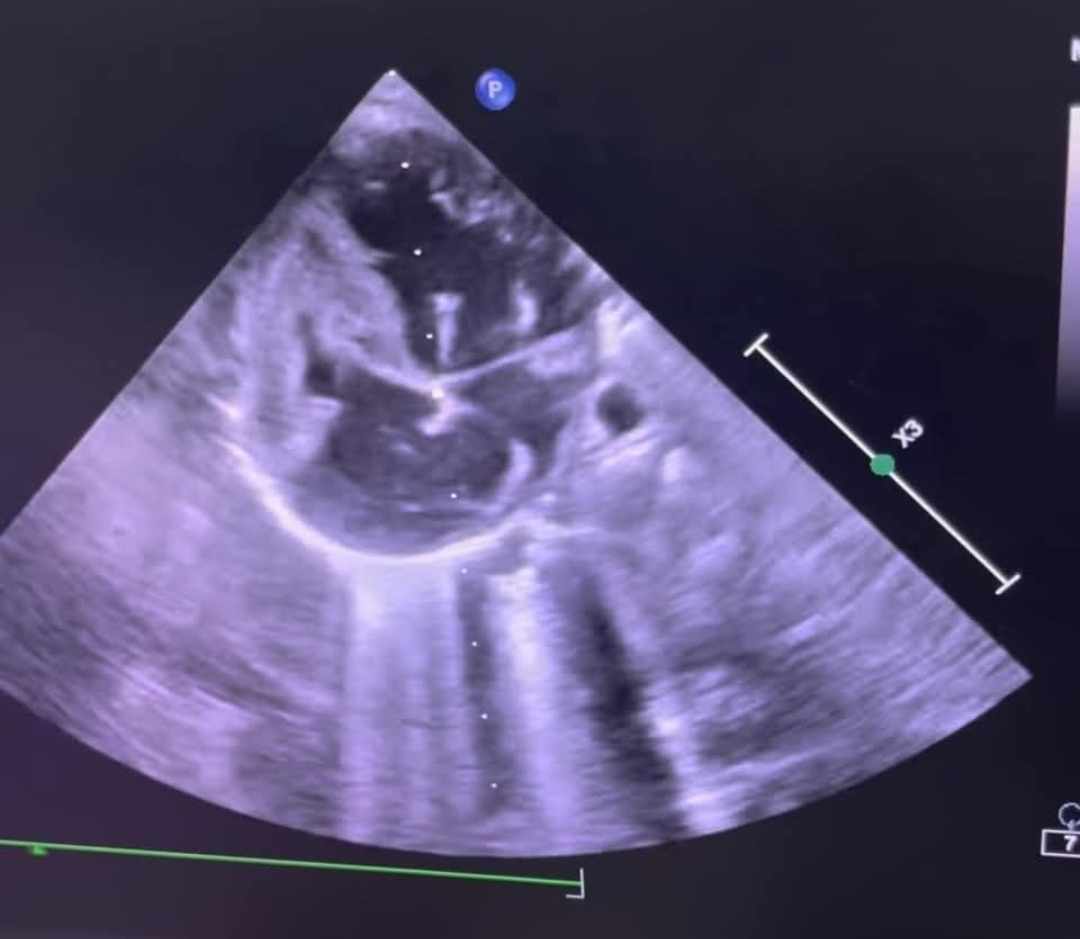

شهدت مستشفى أطفال مصر للتأمين الصحي إنجازًا طبيًا جديدًا يضاف إلى سجلها الحافل في رعاية الأطفال حديثي الولادة، حيث نجح الفريق الطبي بالمستشفى في إجراء أول عملية توسيع للصمام الأورطي بالبالون عن طريق القسطرة لطفلة حديثة الولادة تبلغ من العمر شهرين وتزن 3.600 كجم .

كانت الطفلة تعاني من ضيق شديد بالصمام الأورطي مما تسبب لها في نهجان شديد عند الرضاعة أثر على نموها الطبيعي، حيث تمت العملية الدقيقة بنجاح كبير، وتم نقل الحالة إلى الرعاية المركزة لاستكمال العلاج والمتابعة الطبية، وتتمتع الطفلة الآن بحالة صحية مستقرة وتستعد للخروج والمتابعة الدورية في العيادات الخارجية.